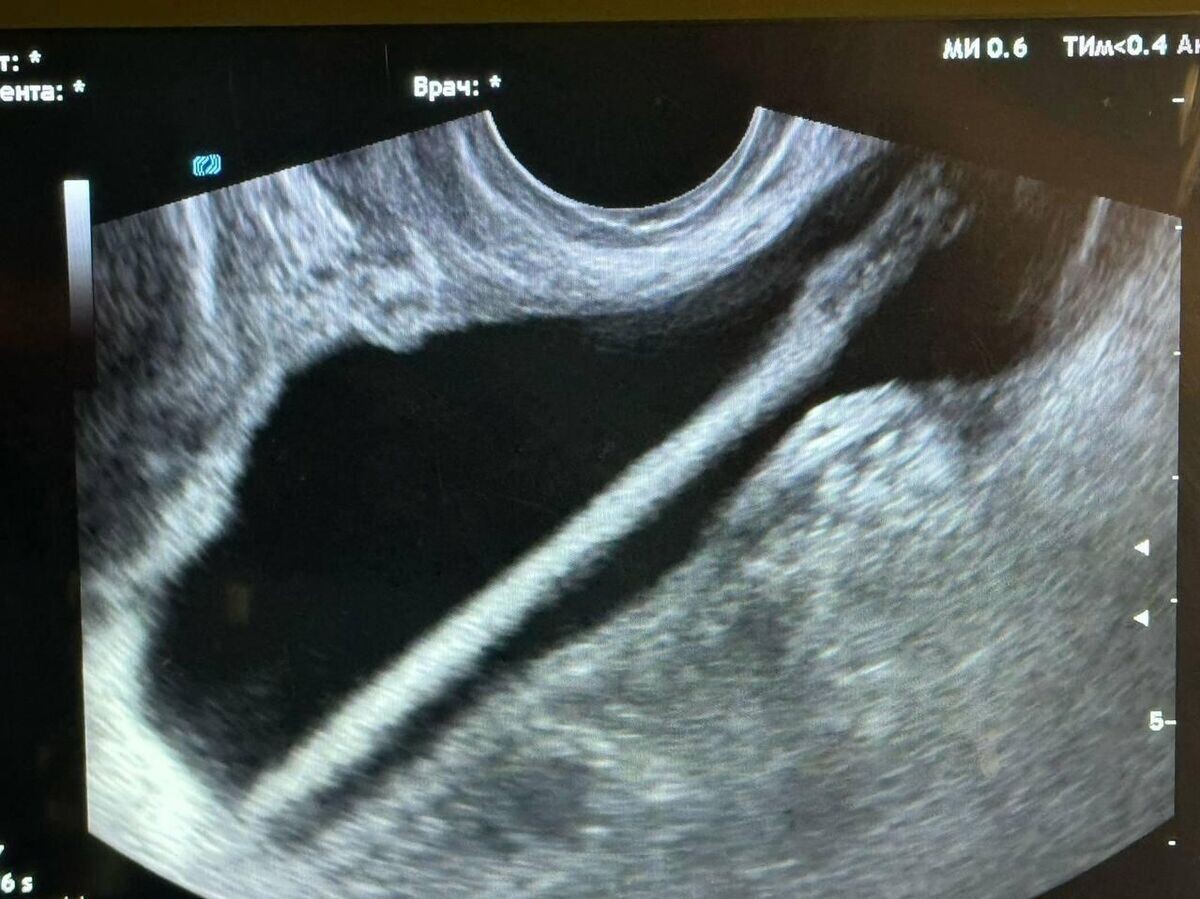

Подмосковные врачи достали из мочевого пузыря пациентки косметический карандаш | © Министерство здравоохранения Московской области

"Сперва в ходе обследования женщине было выполнено УЗИ. После врачи провели оперативное вмешательство, во время которого с помощью эндоскопа они удалили инородное тело из мочевыделительного тракта. Все прошло успешно, без каких-либо осложнений", - рассказал заведующий урологическим отделением Красногорской больницы Петр Сысоев, слова которого приводятся в сообщении.